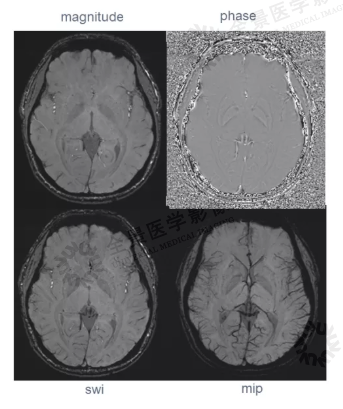

首先介绍了SWI和QSM的成像特点, 重点讲解了QSM 成像在中枢神经系统疾病中的临床应用:显示脑内深部核团的铁质沉积,有助于神经退行性病变的诊断及鉴别诊断;识别脑内微出血,对超急性期出血极为敏感;可鉴别钙化与出血;颅内静脉的显示及血氧饱和度的测量,对脑肿瘤的诊断分级、鉴别诊断与治疗效果评估具有重要意义。

QSM:是在SWI 的基础上发展而来的一种新的图像后处理技术,可对磁敏感物质的磁化率水平进行定量分析,具有高对比度、高分辨力以及对于磁场细微变化的高敏感性,可以无创地揭示病变的病理改变,动态监测病变的发展。